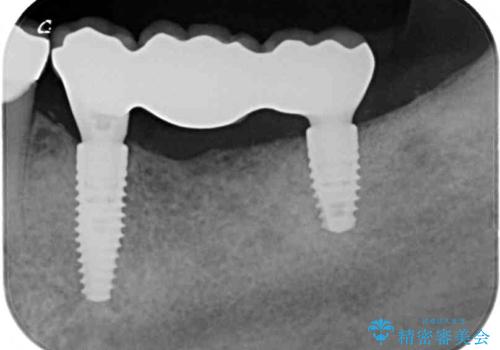

左右ともに歯根が破折しており、抜歯が必要であったため、抜歯後にインプラント補綴治療を行うこととしました。

左側は骨欠損が著しいことが予想されるため、骨造成術並びに歯肉移植術を併用することとしました。